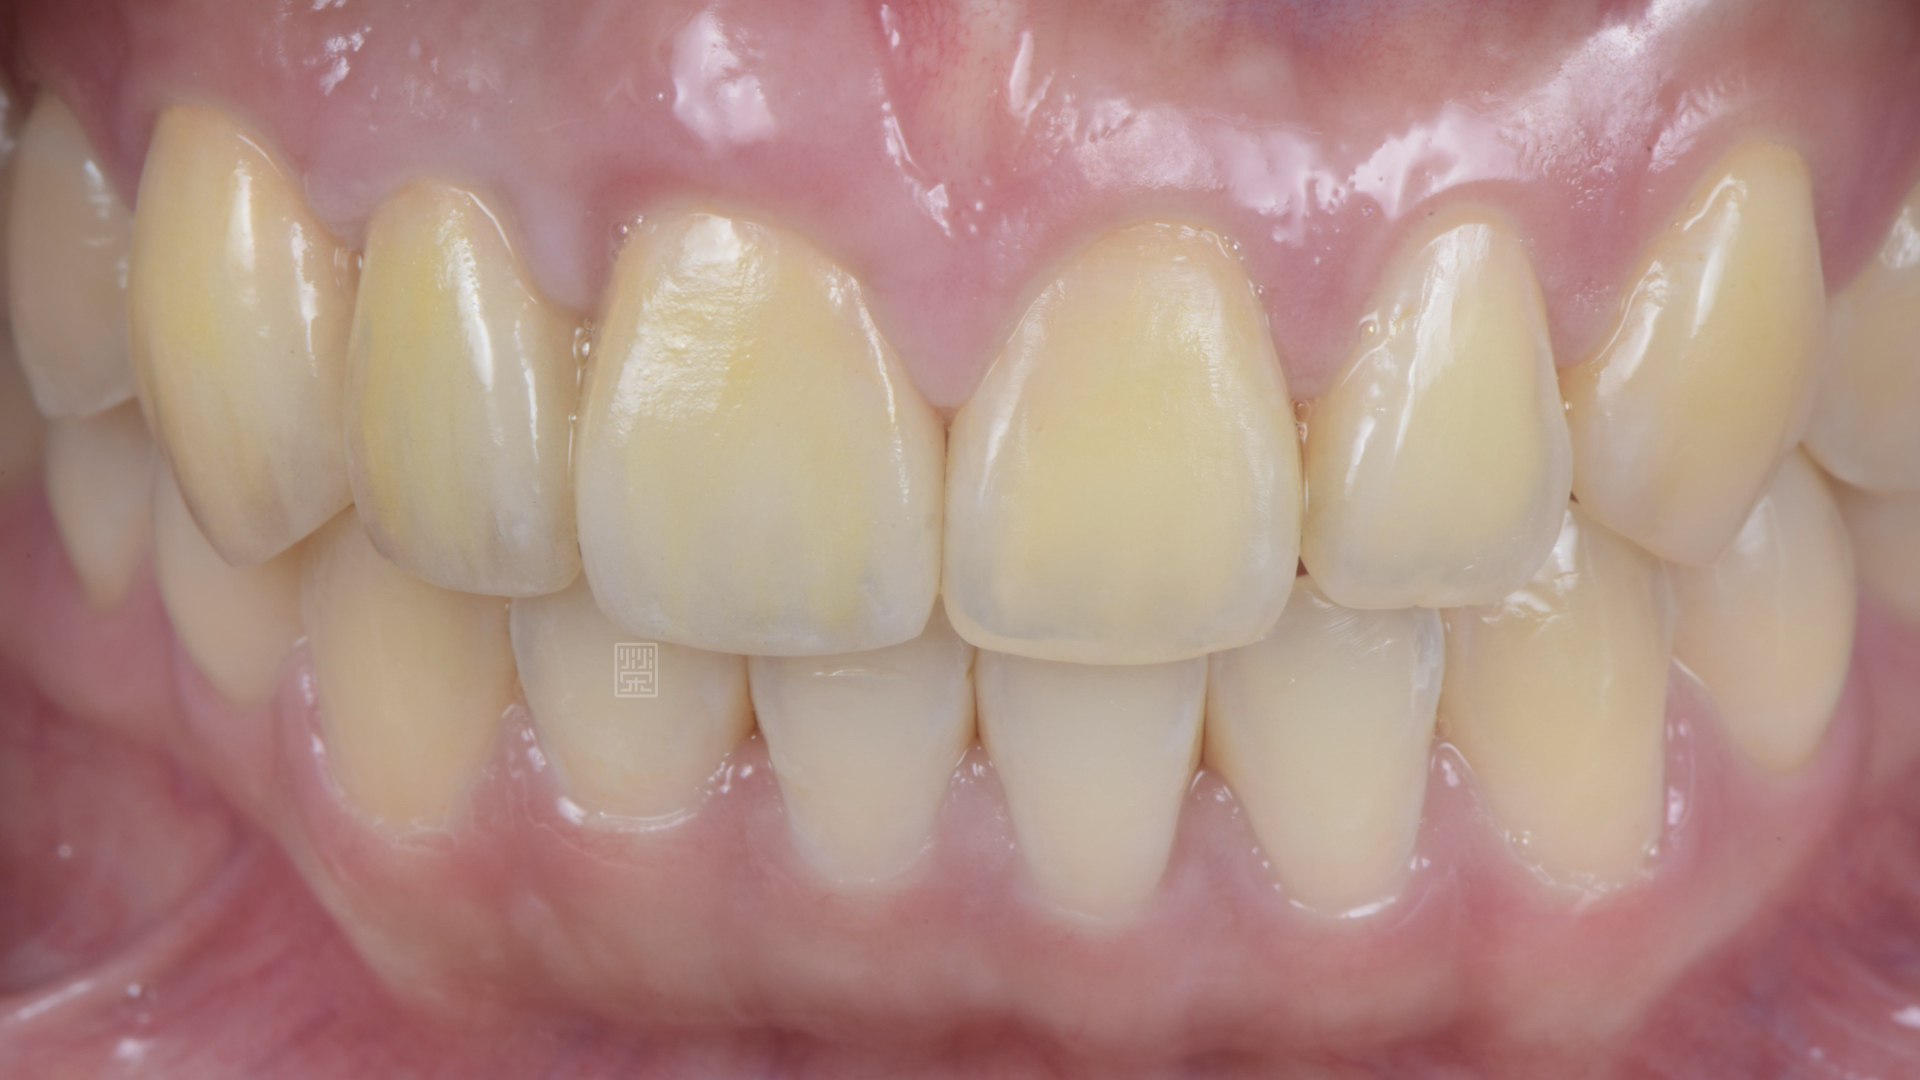

全瓷冠、植牙全瓷冠完成